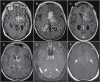

Advanced molecular and pathophysiologic characterization of primary central nervous system lymphoma (PCNSL) has revealed insights into promising targeted therapeutic approaches. Medical imaging plays a fundamental role in PCNSL diagnosis, staging, and response assessment. Institutional imaging variation and inconsistent clinical trial reporting diminishes the reliability and reproducibility of clinical response assessment. In this context, we aimed to: (1) critically review the use of advanced positron emission tomography (PET) and magnetic resonance imaging (MRI) in the setting of PCNSL; (2) provide results from an international survey of clinical sites describing the current practices for routine and advanced imaging, and (3) provide biologically based recommendations from the International PCNSL Collaborative Group (IPCG) on adaptation of standardized imaging practices. The IPCG provides PET and MRI consensus recommendations built upon previous recommendations for standardized brain tumor imaging protocols (BTIP) in primary and metastatic disease. A biologically integrated approach is provided to addresses the unique challenges associated with the imaging assessment of PCNSL. Detailed imaging parameters facilitate the adoption of these recommendations by researchers and clinicians. To enhance clinical feasibility, we have developed both "ideal" and "minimum standard" protocols at 3T and 1.5T MR systems that will facilitate widespread adoption.